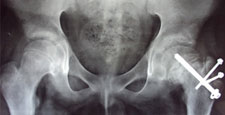

A procedure known as an innominate osteotomy is performed. It takes about 2 hours. The purpose of this operation is to use the normal movement of the hip to mold the soft bone into a round shape.

The bones are moved into the desired position and held together with pins. The pins are removed after 6-12 weeks in a minor operation, usually done on an outpatient basis. After surgery the child is often put into a cast or brace until the joint is stable (i.e., the femoral head well contained).